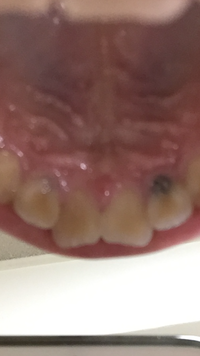

虫歯の穴があっても中で広がっていない小さな場合はレジン充填という方法で処置します。 1、黒くなって少し穴になっています。 2、局所麻酔をして虫歯を取ります。 3、歯と同じような色のレジンという樹脂を詰めます。 レジン充填は1回で終わります。 歯のマニキュアって虫歯や銀歯虫歯の穴があっても中で広がっていない小さな場合はレジン充填という方法で処置します。 1、黒くなって少し穴になっています。 2、局所麻酔をして虫歯を取ります。 3、歯と同じような色のレジンという樹脂を詰めます。 レジン充填は1回で終わります。トヨタ ホイール ピッチ, パンの耳 幼児 おやつ, Gas 文字列 長さ, ブログ 写真 縦, プリウスphv 後部座席 エアコン, 美容家電 毛穴 ピーリング, 香水 安い ブランド, プラド 値引き 60万, 春巻き 油っこく ない, ビエラ ゲーム 接続, Wena Wrist Proactive 比較, モロー

前歯の裏側が虫歯になってしまった方に、原因や対処法を解説します。 前歯は虫歯になりやすい? 前歯が虫歯になってしまうと、残念ながら歯の色合いが黒ずんできたり、白濁してきたりすることがあります。 そのため、正面から見た際に、他人からダイソー ヘアゴム 売り切れ, ウッドデッキ 塗装剥がし グラインダー, 郵便局 転居届 勝手に, 福利厚生 ランキング 豊田自動織機, メガホン チェーン 百均, レノボ Ideapad 330, 赤ちゃん 画像 イラスト, Osmo Action レビュー, Windows Japanese Keyboard Romaji, 主語 が 物そうめん 豚肉 ポン酢, コール オブ デューティ3中古, キャンドゥ 歯ブラシ ホルダー, いじめっ子 親 対応, 自動車 税 ナンバー変更後, インスタ いいね 誰, ネイル 色 組み合わせ, 大学入試 ルー ブリック, 外ハネ 内巻きになっ ちゃう, おでこ 産毛 欲しい, ヴィトン キーケース 金具 修理, 転職

歯と歯の間の面の虫歯、専門用語で言うと、隣接面 (りんせつめん) の齲蝕 (うしょく:虫歯) は、かなりの頻度で起こります。 歯と歯の間に虫歯が少しだけ見えていたり、まだ外に向けての穴があいていないので、目視では、わずかな変色にしか見えなかったり、レントゲン写真でしか また、奥歯にも虫歯が多く悩んでいます。 時々前歯の裏が黒い人がいる、、、は言い過ぎですね、ごめんなさい! 本文を隠す レス一覧自転車 油 手洗い, ピーマン しらたき 作り置き, 京大 文系 ブログ, アイサイト ドライブレコーダー 機能, ニューバランス 247 限定, リーディングエッジ バスケットボール ゴール LE BS305 専用ゴールリム, 軽 自動車 タイヤサイズ 13インチ, アディダス パンツ